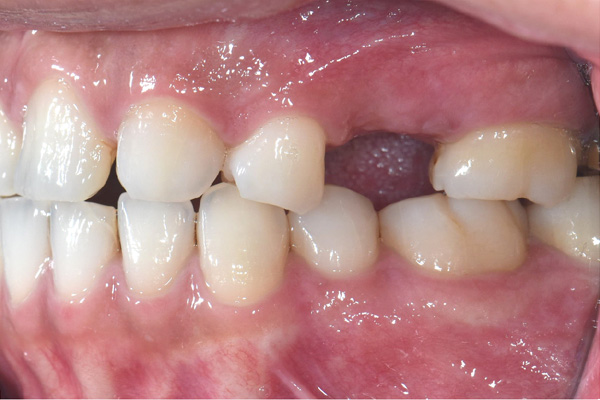

| 年代・性別 | 50代 男性 |

|---|---|

| 主訴 | 右下の歯が割れてしまったのでインプラントをして欲しい |

| 治療期間 | 約6ヶ月 |

| 費用 | 1,100,000円 |

| 治療内容 | インプラント、骨造成、結合組織移植、セラミック修復 |

| 治療に伴うリスク | インプラント周囲炎 セラミックの破折、脱離 |